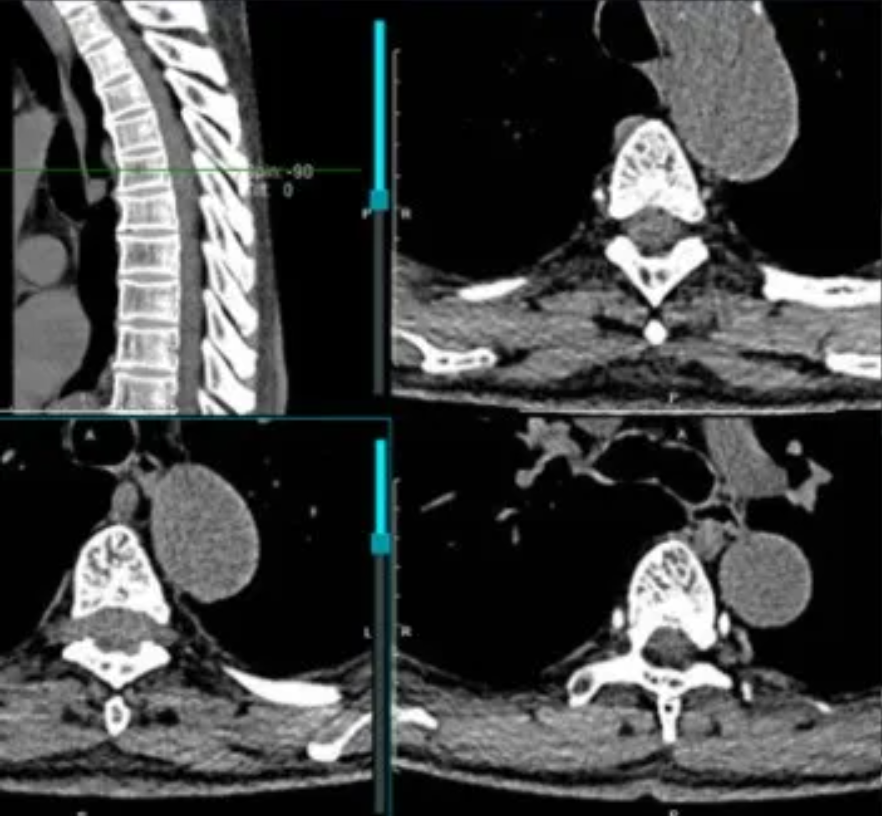

患者男性,62岁,半年前无明显诱因出现胸背部剧烈疼痛,伴下肢无力,严重影响了正常生活。